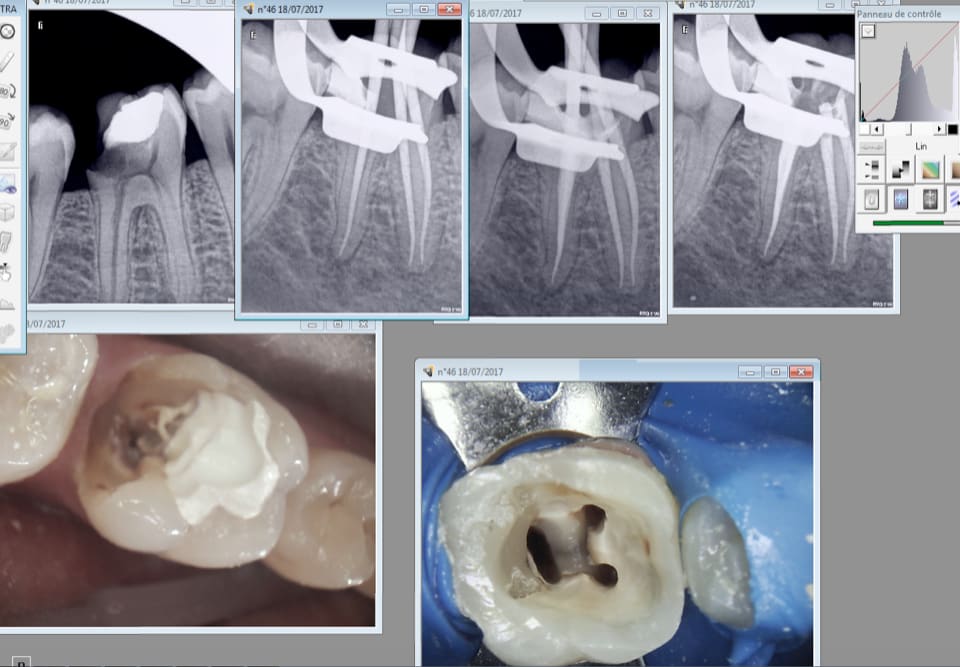

Capture d écran 2017 07 18 12.37 - Eugenol